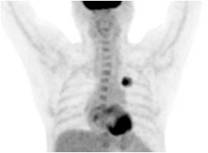

Hình 3: Hình ảnh chụp PET/CT: có khối u thuỳ trên phổi trái với kích thước 2x3cm,

tăng hấp thu F18-FDG không đều, max SUV=6,89. Hạch thượng đòn trái kích thước 0,6x0,7cm.

Chẩn đoán xác định: Ung thư thuỳ trên phổi trái (ung thư biểu mô tuyến), T2N3Mo (Giai đoạn IIIB trên bênh nhân có đợt cấp gút mạn tính).